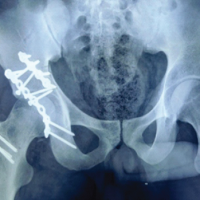

- Standard radiographs: Appeared normal (Fig. 1a)

Figure 1: (a) Representative radiograph demonstrating normal appearance. (b) Transverse magnetic resonance imaging (MRI) image showing high signal intensity within the peroneus brevis tendon at the lateral malleolar level (red arrows). The peroneus longus tendon (blue arrows) appears normal. (c) Coronal MRI image demonstrating a longitudinal tear in the peroneus brevis tendon. (d) Sagittal MRI image demonstrating the longitudinal tear in the peroneus brevis tendon (red arrows) and a normal peroneus longus tendon (black arrow).